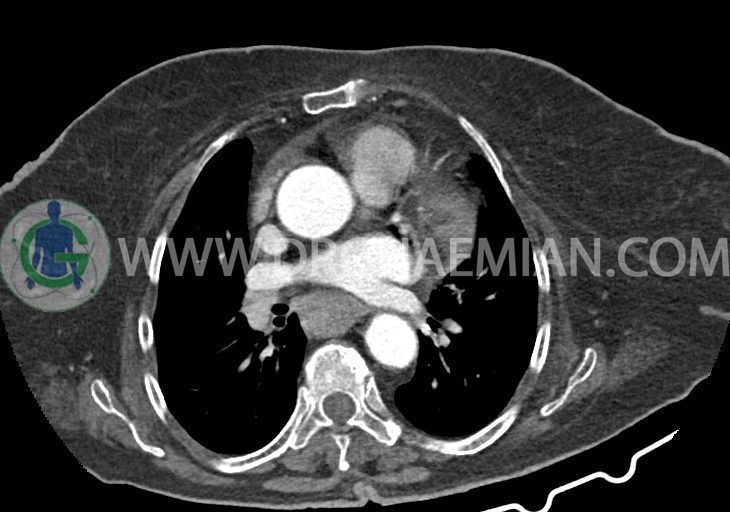

–کاردیومگالی همراه با pericardial effusion خفیف

–آئورت صعودی دیلاته به قطر 38mm

–تغییرات دژنراتیو مهره های توراسیک و اسکولیوز توراکولومبار